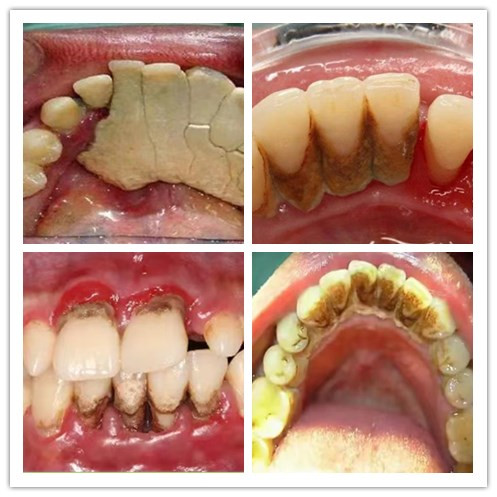

朋友聚会、上台演讲、谈判合作......我们总要笑脸相迎,绕不开交谈、吃喝,如果你的牙齿是这样的,前方高能,图片可能引起不适

牙龈肿痛、牙齿松动,咬物出血,你还能在聚会上侃侃而谈、大快朵颐吗?牙垢烟渍,黄牙黑牙,口腔异味,你还敢与客户畅谈合作,互利共赢吗?

洁牙前,牙结石多,牙龈红肿,色素沉着